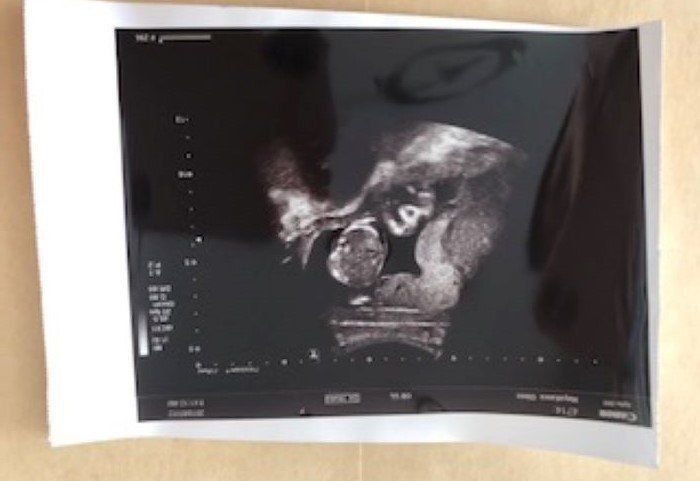

第24週 エコー写真に目線がピッタリ

24w2d

妊娠24週目の健診時、赤ちゃんがバッチリとこちらに向いている時のエコー写真です。エコー検査で見た赤ちゃんは、顔を左右に動かしたり、手足をバタバタと器用に動かしたりと、子宮内の環境にすっかり馴染んでいるように私には見えました。左の写真はパンチをした瞬間です。エコー検査の間も何回か胎動を感じていました。